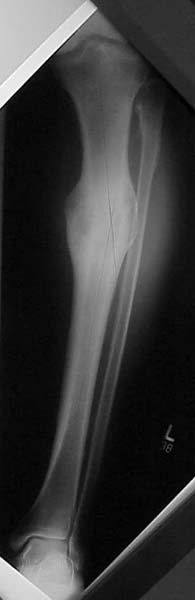

Pt was 10 yrs s/p open tibia fx treated in a cast w/ IR, varus, 2 cm short, and recurvatum. He has done well post op.

preop